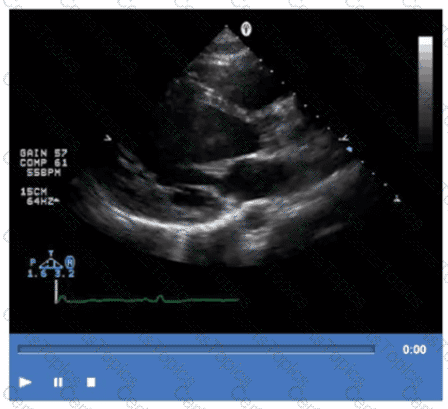

Which pathology is demonstrated in this video clip?

Which of the following is the most likely cause for the findings demonstrated in this video?